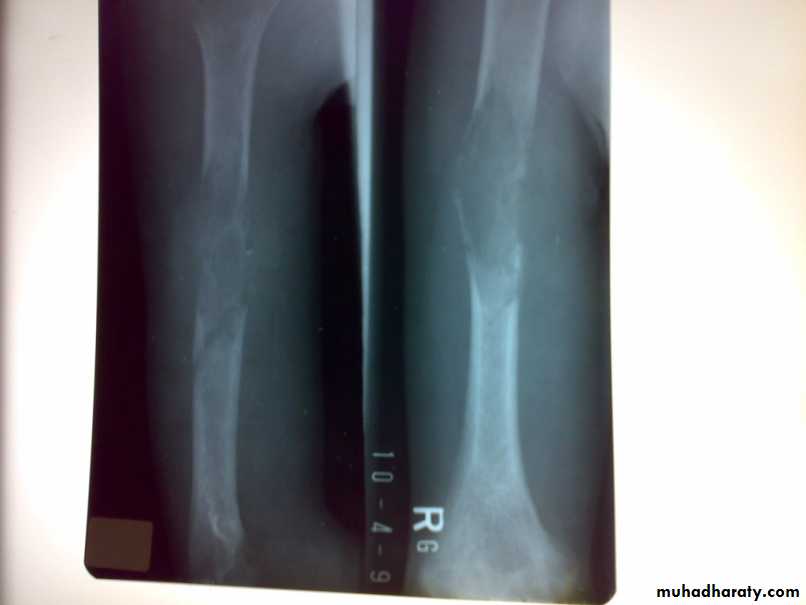

X-ray show eccentric osteolytic lesion in the end of long bone ,subchondral, trabeculated (soap bubble appearance). The cortex is thin, expanded or even perforated.